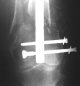

Attached are few examples from our Hospital:

Malpositioning is much too common (recurvatum, varus - valgus).

B. Fixation loosening: distal cutting of the nail, non-unions do happen (cases attached).

Locking Plating has more distal screws than any nail, fixed angles and provides much better fixation, especially in osteoporotic bone.

KEMMD> B. Fixation loosening: distal cutting of the nail, non-unions do happen

The nail can be unlocked in the proximal fragment to prevent it.